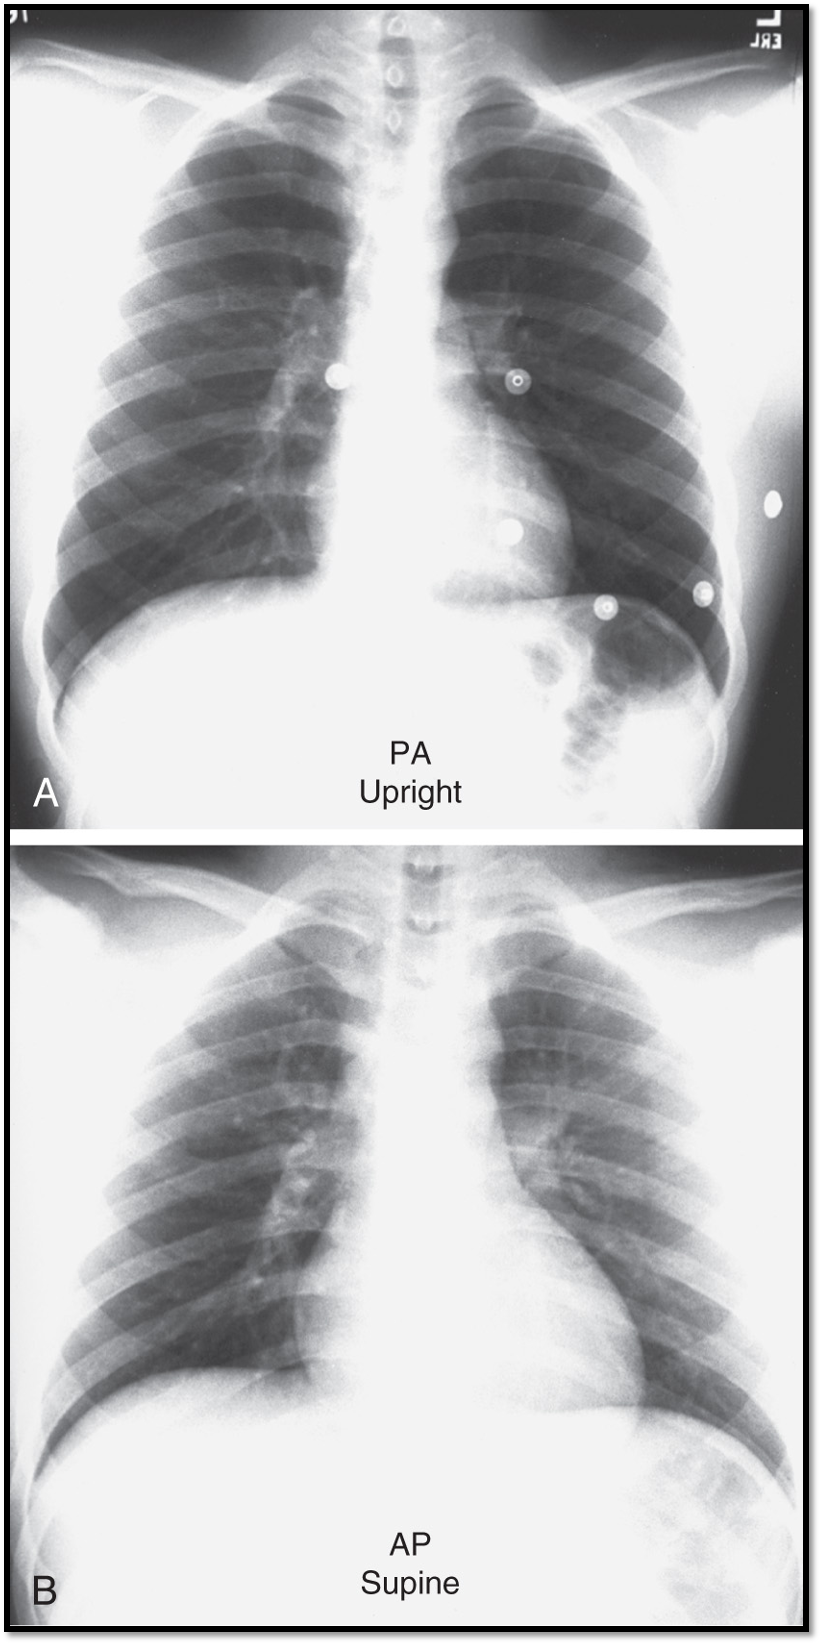

Patient stands upright with chest against detector and beam entering from the back. What projection technique is this?

Posteroanterior (PA) projection

Patient lies supine, with beam entering from front with the detector behind them. What projection technique is this?

Anteroposterior (AP) projection

Main difference between PA vs. AP views?

patient positioning

beam direction

Benefits of upright PA view?

Allows for deeper breaths, producing better lung expansion and clarity of lung fields & provides a more accurate depiction of heart size.

Limitations of supine AP view?

Lungs may appear hypoinflated, lower lung fields may appear hazy, obscuring costophrenic angles and the heart may appear enlarged.

Diagnostic advantages of upright position CXR?

enhanced lung visualization

easier detection of pleural effusions

improved visibility of pneumothoraces

reduced anatomical distortion

Diagnostic limitations of supine CXR?

limited lung inflation

apparent heart enlargement

difficulty detecting smaller pleural effusions and pneumothoraces